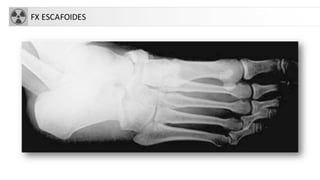

FX ESCAFOIDES

• Escafoides o navicular.

• Fx de la tuberosidad

• Fx con avulsión de la cortical

• Fx por sobrecarga